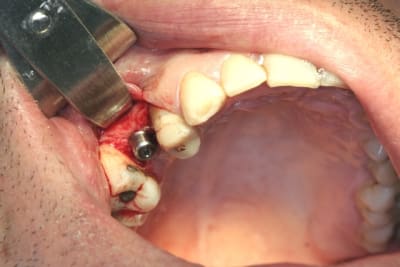

tiens...un ptit cas...

dans ce petit cas...j'ai commencé avec le kit MIS...et fini ma voie crestale avec le kit HBS...

ok, c'est un mini soulevé...mais bon , c'est un exemple...

juste une précision...premier foret 1.3mm sur 8mm...expansion pour mettre un implant de 4x10...

j'ai juste "léché" la préparation du site final avec le foret terminal du système...sur 8mm...avant d'insérer l'implant...stab primaire au top...blocage à 40 Ncm...